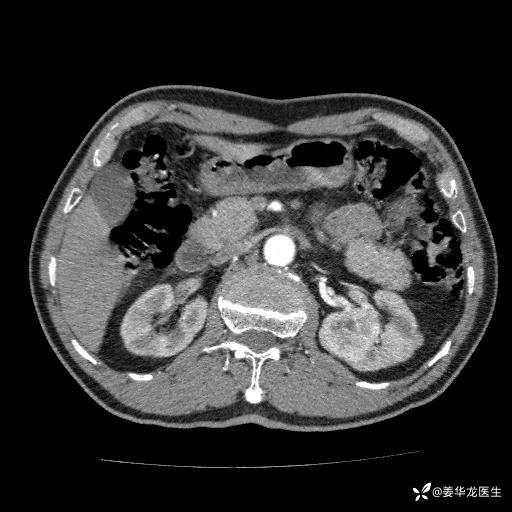

左肾中心型肾门部肿瘤39mm×34mm×36mm,右肾GFR25ml/min,部分切还是全切?

患者75岁老年男性,体重50kg,无高血压、肾病、糖尿病等基础病,检查发现左肾中心型肾门部肿瘤,右肾GFR只有25ml,无肉眼血尿,无镜下血尿。入院验血常规检查均正常,包括肾功能,肌酐102.7umol/L.

二、左肾肿瘤与左肾集合系、左肾动静脉关系密切,左肾部分切除术可行吗?成功率有多大?成功部分切后,肾功能还有多少?